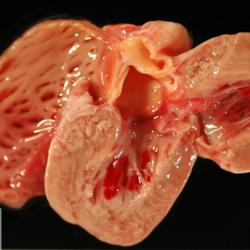

Pàgina anterior de 637 Pàgina següent 3181 total Canine Specie: Canine Organ: Kidney Lesion: Infarction Lesion modifier: - Disease: - Files/Expedient: N-201/15 Position: 252 (1 views) Canine Specie: Canine Organ: Heart Lesion: Endocarditis Lesion modifier: Endocarditis - Valvular Disease: - Files/Expedient: N-201/15 Position: 252 (1 views) Canine Specie: Canine Organ: Heart Lesion: Hemorrhage Lesion modifier: - Disease: Infectious canine hepatitis Files/Expedient: N-583/09 Position: 136 (2 views) Canine Specie: Canine Organ: Liver Lesion: Hepatitis Lesion modifier: Hepatitis - Necrotizing Disease: Infectious canine hepatitis Files/Expedient: N-583/09 Not viewed Canine Specie: Canine Organ: Stomach Lesion: Gastritis Lesion modifier: Gastritis - Hemorrhagic Disease: Infectious canine hepatitis Files/Expedient: N-373/12 Not viewed Pàgina anterior de 637 Pàgina següent Títol Select...Avian (Exotic) (110)Avian (Poultry) (76)Bovine (317)Canine (935)Caprine (47)Equine (257)Feline (326)Ferret (19)General (127)Marine mammal (22)Non-human primate (20)Ovine (328)Porcine (379)Rabbit (61)Reptile (38)Rodent (28)Wildlife (91) Format Select...- (60)Abomasum (37)Adrenal gland (10)Blood (7)Blood vessel (50)Body as a whole (19)Bone (57)Bone marrow (21)Brain (93)Cloaca (1)Diaphragm (2)Ear (5)Esophagus (39)Eye (16)Fetus (12)Gallbladder (23)Gizzard (2)Heart (265)Intestine (356)Joint (32)Kidney (443)Larynx (5)Liver (326)Lung (264)Lymph node (91)Mammary gland (10)Mediastinum (1)Muscle (22)Nasal cavity (22)Nerve (7)Omasum (5)Oral cavity (63)Ovary (14)Oviduct (8)Pancreas (7)Parathyroid (5)Penis (10)Peritoneum (65)Pharynx (9)Pituitary gland (6)Placenta (7)Prostate (8)Proventriculus (3)Reticulum (1)Rumen (28)Sinus (7)Skin (181)Spinal cord (15)Spleen (105)Stomach (125)Teeth (1)Testicle (11)Thoracic cavity (31)Thymus (13)Thyroid gland (5)Tongue (32)Tonsils (11)Trachea (11)Urethra (5)Urinay bladder (61)Uterus (27)Vagina (1)Vulva (1)Yolk sac (1) Cobertura Select...- (152)Abomasitis (26)Abscess (27)Acidosis (1)Adenocarcinoma (20)Adenoma (9)Aerosacculitis (6)Agenesis (1)Agnathia (1)Alopecia (7)Amyloidosis (12)Aneurysm (6)Angiectasis (1)Anthracosis (1)Arteritis (11)Arthritis (15)Arthrogryposis (6)Artifact (4)Ascites (13)Atelectasis (8)Atherosclerosis (5)Atresia (1)Atrial septal defect (2)Atrophy (10)Autolysis (7)Bronchitis (6)Bronchopneumonia (26)Cachexia (2)Carcinoma (103)Cardiomyopathy (19)Cellulitis (2)Chemodectoma (4)Cholangiohepatitis (4)Cholangitis (19)Cholecystitis (4)Cholestasis (5)Chondrodysplasia (2)Chondrosarcoma (2)Chronic passive congestion (13)Chylothorax (2)Cirrhosis (6)Coelomitis (3)Coenurus cerebralis (4)Colitis (40)Congestion (17)Conjunctivitis (5)Coronitis (3)Cryptorchidism (3)Cyst (25)Cystitis (24)Dermatitis (69)Diaphragmatic hernia (4)Dilation (28)Discospondylitis (1)Disseminated intravascular coagulation (7)Dyschondroplasia (1)Dysplasia (29)Ectopia cordis (1)Ectopic ureter (1)Edema (55)Emphysema (5)Encephalitis (5)Endocardiosis (14)Endocarditis (26)Endometritis (5)Enteritis (118)Enterolith (6)Epulis (3)Esophagitis (14)Fasciitis (1)Fibrosis (7)Fibrous osteodystrophy (8)Fistula (1)Folliculitis (3)Fracture (2)Gastritis (34)Gingivitis (5)Glioma (8)Glomerulonephritis (21)Glossitis (25)Glycogenosis (1)Gout (8)Granuloma (2)Granulosa cell tumor (4)Hemangioma (9)Hemangiosarcoma (46)Hematoma (8)Hemoglobinuria (2)Hemopericardium (12)Hemoperitoneum (2)Hemorrhage (100)Hemosiderosis (7)Hemothorax (2)Hepatitis (78)Hernia (11)Histiocytosis (3)Hydatid cyst (11)Hydrocephalus (9)Hydrometra (1)Hydronephrosis (22)Hydropericardium (6)Hydrothorax (3)Hydroureter (5)Hyperkeratosis (8)Hyperostosis (4)Hyperplasia (37)Hypertrophy (9)Hypopigmentation (1)Hypoplasia (7)Hypopyon (1)Impaction (6)Infarction (63)Insulinoma (6)Intussusception (5)Jaundice (17)Laminitis (2)Laryngitis (2)Leiomyoma (5)Leukemia (13)Lipidosis (36)Lipoma (7)Lymphadenitis (45)Lymphadenopathy (7)Lymphangiectasia (6)Lymphangitis (5)Lymphoma (221)Malacia (11)Malignant melanoma (15)Mast cell tumor (11)Mastitis (8)Megaesophagus (2)Melanosis (3)Melena (4)Meningioma (6)Meningitis (6)Meningocele (2)Meningoencephalitis (5)Mesothelioma (5)Methemoglobinemia (2)Mineralization (10)Mucocele (5)Mucometra (1)Multilobular bone tumor (1)Mummification (3)Myelofibrosis (1)Myocarditis (4)Myositis (5)Necrosis (81)Nephritis (113)Nephroblastoma (6)Nephrosclerosis (1)Nephrosis (14)Neuritis (1)Obstruction (13)Omasitis (4)Omphalitis (1)Omphalophlebitis (7)Orchitis (4)Osteoarthrosis (5)Osteomyelitis (9)Otitis (2)Palatoschisis (3)Pancreatitis (3)Panniculitis (3)Papilloma (7)Parakeratosis (14)Patent ductus arteriosus (6)Peliosis hepatis (1)Perforation (17)Pericarditis (35)Peritonitis (39)Persistent right aortic arch (1)Pharyngitis (2)Pheochromocytoma (2)Phlebitis (2)Placentitis (6)Pleuritis (21)Pleuropneumonia (24)Pneumonia (109)Pneumothorax (3)Polycystosis (14)Polyp (5)Polyserositis (6)Posthitis (1)Proctitis (4)Prolapse (3)Prostatitis (3)Proventriculitis (1)Pyelonephritis (24)Pyometra (6)Pyothorax (4)Rhinitis (11)Rumenitis (6)Rupture (24)Salpingitis (3)Sarcoma (57)Sclerosis (1)Scoliosis (2)Seminoma (2)Sequestrum (2)Serous atrophy (14)Sinusitis (7)Splenitis (14)Splenomegaly (9)Spondylitis (6)Spondylosis (1)Stenosis (9)Stomatitis (32)Tenosynovitis (2)Teratoma (3)Thricobezoar (2)Thrombosis (16)Tonsilitis (4)Torsion (13)Tracheitis (4)Tympany (7)Typhlitis (8)Typhlocolitis (4)Ulcer (43)Urethritis (1)Urolithiasis (36)Uroperitoneum (1)Uveitis (1)Vasculitis (15)Ventricular septal defect (3)Volvulus (11) Matèria Select... - (14)- (1653)- (152)Abomasitis - Catarrhal (2)Abomasitis - Catarrhal-hemorrhagic (1)Abomasitis - Chronic (1)Abomasitis - Fibrinous-necrotizing (2)Abomasitis - Hyperplasic (5)Abomasitis - Hyperplasic - Chronic (1)Abomasitis - Necrotic (1)Abomasitis - Necrotizing (2)Abomasitis - Ulcerative (5)Adenocarcinoma (9)Aerosacculitis - Granulomatous (1)Amyloidosis - Chronic (1)Arteritis - Necrotic (2)Arteritis - Necrotizing (1)Arthritis - Chronic (4)Arthritis - Fibrinous-purulent (3)Arthritis - Serous (4)Arthritis - Subacute (1)Ascites - Serous (1)Atrophy - Serous (1)Bronchitis - Catarrhal (3)Bronchitis - Suppurative (1)Bronchopneumonia - Catarrhal-purulent (17)Bronchopneumonia - Fibrinous (1)Bronchopneumonia - Granulomatous (1)Bronchopneumonia - Purulent (1)Bronchopneumonia - Suppurative (5)Carcinoma - Adenocarcinoma (33)Carcinoma - Adenocarcinoma - Hepatocellular (2)Carcinoma - Adenocarcinoma - Mucinous (1)Carcinoma - Basosquamous (1)Carcinoma - Cholangiocellular (3)Carcinoma - Hepatocellular (4)Carcinoma - Metastatic (3)Carcinoma - Squamous cell carcinoma (13)Carcinoma - Transitional cell (2)Cardiomyopathy - Dilated (13)Cardiomyopathy - Hypertrophic (6)Cellulitis - Necrotizing (1)Cholangitis - Chronic (8)Cholangitis - Hyperplasic (3)Cholecystitis - Fibrinous-necrotizing (1)Coelomitis - Fibrinous (1)Coelomitis - Granulomatous (1)Colitis - Catarrhal (3)Colitis - Catarrhal-hemorrhagic (1)Colitis - Fibrinous (1)Colitis - Fibrinous-necrotizing (1)Colitis - Fibrinous-necrotizing (Diphtheritic) (6)Colitis - Granulomatous (2)Colitis - Hemorrhagic (4)Colitis - Hemorrhagic-necrotizing (3)Colitis - Necrotizing (2)Colitis - Ulcerative (6)Congestion - Chronic (2)Conjunctivitis - Hyperplasic (1)Conjunctivitis - Purulent (3)Coronitis - Ulcerative (1)Cystitis - Chronic (3)Cystitis - Fibrinous (1)Cystitis - Fibrinous-necrotizing (1)Cystitis - Follicular (1)Cystitis - Hemorrhagic (6)Cystitis - Hemorrhagic-ulcerative (1)Cystitis - Necrotizing (9)Cystitis - Perforated (1)Dermatitis - Granulomatous (14)Dermatitis - Hyperkeratotic (10)Dermatitis - Hyperplasic (proliferative) (1)Dermatitis - Hyperplastic (10)Dermatitis - Necrotizing (4)Dermatitis - Pustular (4)Dermatitis - Ulcerative (2)Dilation - Chronic (1)Discospondylitis - Necrotizing (1)Dysplasia - Follicular (5)Edema - Interstitial (6)Emphysema - Interstitial (1)Encephalitis - Granulomatous (1)Encephalitis - Nonsuppurative (1)Endocardiosis - Mitral (7)Endocardiosis - Mitral - Chronic (5)Endocarditis - Valvular (6)Endocarditis - Valvular - Mitral (7)Endocarditis - Valvular - Pulmonic (1)Endocarditis - Valvular - Subacute (1)Endocarditis - Valvular - Subaortic (5)Endocarditis - Valvular - Tricuspid (4)Endometritis - Purulent (3)Endometritis - Purulent-hemorrhagic (2)Enteritis - Catarrhal (23)Enteritis - Catarrhal - Acute (1)Enteritis - Catarrhal-hemorrhagic (5)Enteritis - Catarrhal-hemorrhagic - Acute (2)Enteritis - Fibrinous (16)Enteritis - Fibrinous - Acute (3)Enteritis - Fibrinous-necrotizing (7)Enteritis - Granulomatous (14)Enteritis - Granulomatous - Chronic (1)Enteritis - Granulomatous - Multifocal (1)Enteritis - Hemorrhagic (17)Enteritis - Hemorrhagic - Acute (1)Enteritis - Hemorrhagic-necrotizing (1)Enteritis - Hyperplasic (proliferative) (4)Enteritis - Necrotizing (4)Enteritis - Necrotizing - Acute (1)Enteritis - Necrotizing - Hemorrhagic (1)Enteritis - Necrotizing-ulcerative (2)Enteritis - Ulcerative (1)Enteritis - Ulcerative-hemorrhagic (1)Esophagitis - Erosive-ulcerative (6)Esophagitis - Necrotizing (4)Esophagitis - Ulcerative (1)Esophagitis - Ulcerative-necrotizing (1)Fasciitis - Fibrinous-purulent (1)Folliculitis - Purulent (2)Gastritis - Catarrhal (2)Gastritis - Chronic (1)Gastritis - Follicular (1)Gastritis - Hemorrhagic (2)Gastritis - Hemorrhagic-necrotizing (1)Gastritis - Hypertrophic (2)Gastritis - Inclusion bodies (1)Gastritis - Mineralization (1)Gastritis - Mycotic (1)Gastritis - Necrotizing (2)Gastritis - Ulcerative (6)Gastritis - Uremic (3)Gingivitis - Erosive (2)Gingivitis - Hyperplasic (proliferative) (1)Gingivitis - Necrotizing (1)Glomerulonephritis - Chronic (7)Glomerulonephritis - Membranoproliferative (3)Glomerulonephritis - Membranoproliferative - Chronic (1)Glomerulonephritis - Membranous (3)Glomerulonephritis - Membranous - Chronic (1)Glomerulonephritis - Proliferative (2)Glomerulonephritis - Subacute (1)Glossitis - Erosive (2)Glossitis - Granulomatous (6)Glossitis - Hyperplasic (1)Glossitis - Hyperplasic (proliferative) (2)Glossitis - Hyperplastic (1)Glossitis - Necrotizing (2)Glossitis - Necrotizing - Focal (1)Glossitis - Ulcerative (6)Glossitis - Ulcerative - Multifocal (1)Glossitis - Ulcerative - Subacute (1)Glycogenosis (1)Granuloma - Eosinophilic (1)Hemangiosarcoma - Metastatic (2)Hemorrhage - Acute (1)Hemorrhage - Subcapsular (3)Hepatitis - Abscess (9)Hepatitis - Acute (3)Hepatitis - Chronic (4)Hepatitis - Chronic interstitial (6)Hepatitis - Granulomatous (7)Hepatitis - Interstitial - Multifocal (1)Hepatitis - Interstitial - Subacute (1)Hepatitis - Necrotizing (17)Hepatitis - Necrotizing - Acute (2)Hepatitis - Necrotizing - Hemorrhagic (1)Hepatitis - Necrotizing - Subacute (1)Hepatitis - Pyogranulomatous (7)Hepatitis - Subacute (4)Hydronephrosis - Chronic (1)Hydropericardium - Chronic (1)Hyperplasia - Erythroid (1)Hyperplasia - Lymphoid (3)Hyperplasia - Myeloid (1)Hyperplasia - Nodular (8)Hypertrophy - Concentric (2)Hypertrophy - Eccentric (3)Infarction - Acute (17)Infarction - Acute - Multifocal (2)Infarction - Chronic (5)Infarction - Chronic - Multifocal (1)Infarction - Subacute (18)Infarction - Subacute - Focal (2)Laminitis - Chronic (2)Laryngitis - Necrotic (1)Laryngitis - Necrotizing (1)Leukemia - Lymphoid leukemia (2)Leukemia - Non-lymphoid leukemia (6)Lipidosis - Multifocal (1)Lipidosis - Panlobular (1)Lipidosis - Panlobular - Generalized (2)Lymphadenitis - Granulomatous (24)Lymphadenitis - Granulomatous - Chronic (3)Lymphadenitis - Hemorrhagic (1)Lymphadenitis - Necrotizing (5)Lymphadenitis - Necrotizing (caseous) (11)Lymphangitis - Granulomatous (1)Lymphangitis - Purulent (1)Lymphangitis - Ulcerative (1)Lymphoma - Alimentary lymphoma (7)Lymphoma - Cutaneous lymphoma (6)Lymphoma - Lymphosarcoma (2)Lymphoma - Mediastinal lymphoma (1)Lymphoma - Multicentric lymphoma (29)Malignant melanoma - Malignant (1)Malignant melanoma - Metastatic (1)Mast cell tumor - Metastatic (1)Mastitis - Fibrinous-purulent (2)Mastitis - Necrotic (1)Mastitis - Purulent (3)Mastitis - Suppurative (1)Meningitis - Fibrinous-purulent (2)Meningitis - Purulent (4)Meningoencephalitis - Necrotizing (3)Meningoencephalitis - Nonsuppurative (2)Mineralization - Metastatic (4)Myocarditis - Fibrous - Chronic (1)Myocarditis - Granulomatous (1)Myositis - Purulent (2)Necrosis - Acute (1)Necrosis - Cortical (5)Necrosis - Follicular (1)Necrosis - Papillary (8)Necrosis - Papillary - Acute (3)Necrosis - Subacute (3)Necrosis - Tubular (6)Nephritis - Embolic (2)Nephritis - Embolic suppurative (7)Nephritis - Granulomatous (27)Nephritis - Granulomatous - Chronic (1)Nephritis - Granulomatous - Multifocal (1)Nephritis - Interstitial (6)Nephritis - Interstitial - Acute (4)Nephritis - Interstitial - Chronic (41)Nephritis - Interstitial - Subacute (12)Nephritis - Purulent (7)Nephritis - Purulent - Acute (2)Nephritis - Purulent - Multifocal (3)Nephrosis - Cholemic (3)Nephrosis - Hemoglobinuric (10)Omasitis - Fibrinous-necrotizing (1)Omasitis - Hyperkeratotic (1)Omasitis - Necrotizing (2)Omphalophlebitis - Fibrinous-purulent (2)Omphalophlebitis - Purulent (3)Orchitis - Necrotizing (1)Osteomyelitis - Necrotizing (7)Osteomyelitis - Purulent (2)Otitis - Necrotizing (1)Otitis - Proliferative (1)Pancreatitis - Acute (1)Pancreatitis - Chronic (1)Pancreatitis - Granulomatous (1)Panniculitis - Fibrinous-purulent (1)Panniculitis - Necrotic (1)Panniculitis - Parasitic (1)Perforation - Acute (2)Pericarditis - Fibrinous (19)Pericarditis - Fibrinous - Subacute (1)Pericarditis - Fibrinous-necrotizing (1)Pericarditis - Fibrinous-purulent (3)Pericarditis - Fibrous (1)Pericarditis - Fibrous - Chronic (1)Pericarditis - Gangrenous (6)Pericarditis - Granulomatous (1)Pericarditis - Granulomatous - Chronic (2)Peritonitis - Acute (1)Peritonitis - Fibrinous (11)Peritonitis - Fibrinous - Subacute (1)Peritonitis - Fibrinous-purulent (5)Peritonitis - Fibrous (3)Peritonitis - Granulomatous (6)Peritonitis - Purulent (1)Peritonitis - Purulent-hemorrhagic (1)Peritonitis - Pyogranulomatous (3)Pharyngitis - Fibrinous-necrotizing (1)Pharyngitis - Ulcerative (1)Pheochromocytoma - Metastatic (1)Phlebitis - Purulent (1)Placentitis - Fibrinous-necrotizing (1)Placentitis - Necrotic (1)Placentitis - Necrotizing (1)Pleuritis - Chronic (1)Pleuritis - Fibrinous (3)Pleuritis - Fibrinous-purulent (2)Pleuritis - Fibrous (2)Pleuritis - Granulomatous (3)Pleuritis - Hyperplastic (2)Pleuritis - Purulent (2)Pleuritis - Pyogranulomatous (1)Pleuropneumonia - Fibrinous (13)Pleuropneumonia - Fibrinous-necrotizing (5)Pleuropneumonia - Granulomatous (2)Pleuropneumonia - Hemorrhagic-necrotizing (4)Pneumonia - Aspiration (11)Pneumonia - Bronchointerstitial (4)Pneumonia - Bronchointerstitial - Subacute (1)Pneumonia - Embolic (5)Pneumonia - Granulomatous (37)Pneumonia - Granulomatous - Multifocal (4)Pneumonia - Hemorrhagic-necrotizing (2)Pneumonia - Interstitial (7)Pneumonia - Interstitial - Acute (8)Pneumonia - Interstitial - Chronic (6)Pneumonia - Interstitial - Subacute (15)Pneumonia - Necrotizing (2)Pneumonia - Pyogranulomatous (2)Pneumonia - Verminous (5)Polyserositis - Fibrinous (6)Polyserositis - Fibrous (1)Proctitis - Fibrinous-necrotizing (1)Proctitis - Parasitic (2)Prostatitis - Purulent (1)Pyelonephritis - Acute (2)Pyelonephritis - Chronic (3)Rhinitis - Catarrhal (2)Rhinitis - Fibrinous (1)Rhinitis - Granulomatous (4)Rhinitis - Purulent (3)Rumenitis - Acute (1)Rumenitis - Erosive (1)Rumenitis - Necrotizing (1)Rupture - Acute (3)Sarcoma - Fibrosarcoma (12)Sarcoma - Hemangiosarcoma (11)Sarcoma - Histiocytic (7)Sarcoma - Metastatic (1)Sarcoma - Multilobular tumor of bone (1)Sequestrum - Chronic (2)Sinusitis - Suppurative (1)Splenitis - Granulomatous (8)Splenitis - Granulomatous - Chronic (1)Splenitis - Necrotizing (3)Splenitis - Necrotizing (caseous) (2)Spondylitis - Necrotizing (2)Stenosis - Intestinal (1)Stenosis - Valvular - Subaortic (4)Stomatitis - Erosive (12)Stomatitis - Erosive-ulcerative (3)Stomatitis - Fibrinous-necrotizing (1)Stomatitis - Fibrinous-necrotizing (Diphtheritic) (1)Stomatitis - Granulomatous (1)Stomatitis - Hyperplasic (1)Stomatitis - Hyperplasic (proliferative) (1)Stomatitis - Necrotizing (2)Stomatitis - Ulcerative (5)Stomatitis - Ulcerative - Multifocal (1)Stomatitis - Ulcerative-necrotizing (1)Tonsilitis - Necrotizing (4)Torsion - Acute passive hyperemia (5)Tracheitis - Catarrhal (3)Tracheitis - Fibrinous (1)Tracheitis - Granulomatous (1)Typhlitis - Catarrhal (1)Typhlitis - Fibrinous-necrotizing (2)Typhlitis - Hemorrhagic (2)Typhlitis - Ulcerative-hemorrhagic (1)Typhlocolitis - Fibrinous-necrotizing (2)Typhlocolitis - Proliferative (1)Ulcer - Chronic (6)Ulcer - Multifocal (2)Ulcer - Mycotic (1)Ulcer - Perforated (6)Urethritis - Hemorrhagic (1)Urolithiasis - Chronic (2)Uveitis - Granulomatous (1)Vasculitis - Granulomatous (1)Vasculitis - Necrotizing (1) Editor Select...- (1970)Acidosis (2)Actinobacillosis (Pleuropneumonia) (11)Aelurostrongylosis (2)African horse sickness (13)African swine fever (14)Alopecia X (1)Anaplasmosis (4)Anthrax (2)Aortic thromboembolism (feline) (7)Ascariasis (15)Aspergillosis (18)Atopic dermatitis (1)Atrophic rhinitis (3)Babesiosis (6)Blackhead (1)Bluetongue (11)Border disease (2)Bovine viral diarrhea (21)Brucellosis (2)Candidiasis (5)Canine distemper (14)Caprine arthritis-encephalitis (2)Capture myopathy (1)Cardiac insufficiency (17)Caseous lymphadenitis (7)Chlamydiosis (2)Classical swine fever (19)Clostridiosis (19)Coccidiosis (9)Coenurosis (4)Colibacillosis (21)Contagious ecthyma (7)Copper toxicosis (11)Cowdriosis (Heartwater) (3)Cryptococcosis (3)Cryptosporidiosis (2)Cysticercosis (23)Demodicosis (1)Diabetes (1)Dicrocoeliosis (5)Dictyocaulosis (4)Dirofilariasis (7)Discoid lupus erythematosus (3)Echinococcosis (17)Edema disease (7)Egg drop syndrome (1)Encephalitozoonosis (5)Enterotoxemia (1)Enzootic bovine leukosis (46)Epitheliogenesis imperfecta (3)Equine rhinopneumonitis (2)Equine verminous arteritis (strongylosis) (7)Erysipelas (5)Exudative epidermitis (7)Fasciolasis (11)Feline eosinophilic dermatoses (1)Feline hepatic lipidosis (8)Feline histiocytosis (4)Feline infectious peritonitis (38)Feline leukemia (4)Feline lower urinary tract disease (3)Feline panleukopenia (16)Feline viral rhinotracheitis (1)Flea allergy dermatitis (1)Foot and mouth disease (2)Gasterophilosis (4)Glasser's disease (15)Gousiekte (4)Gout (6)Haemonchosis (9)Hemolytic anemia (4)Hemorrhagic diathesis (1)Hepatic insufficiency (11)Hepatosis dietetica (7)Herpesvirosis (6)Hyperadrenocorticism (7)Hyperparathyroidism (10)Hypertrophic osteopathy (6)Hypervitaminosis D (1)Hypodermosis (1)Inclusion body hepatitis (4)Infectious bovine rhinotracheitis (5)Infectious bronchitis (5)Infectious canine hepatitis (13)Influenza (4)Juvenile nephropathy (8)Lamb dysentery (4)Leishmaniasis (28)Leptospirosis (1)Leukosis (5)Listeriosis (4)Lumpy skin disease (3)Maedi-visna (4)Malignant catarrhal fever (12)Mange (6)Mannheimiosis (5)Marek's disease (7)Metabolic bone disease (2)Mucoid enteropathy (5)Mulberry heart disease (5)Myasis (1)Mycobacteriosis (22)Mycosis fungoides (6)Myxomatosis (3)Necrobacillosis (5)Neonatal isoerythrolysis (6)Nocardiosis (4)Oestrosis (2)Onchocerciasis (1)Osteochondrosis (1)Ostertagiosis (6)Ovine pulmonary adenocarcinoma (5)Oxyuriasis (1)Pacheco's disease (4)Papillomatosis (6)Paratuberculosis (18)Parvovirosis (17)Pasteurellosis (11)Pemphigus foliaceus (1)Periodontal disease (1)Polioencephalomalacia of ruminants (4)Polyarteritis nodosa (3)Polycystic kidney disease (13)Porcine circovirosis (11)Porcine dermatitis and nephropathy syndrome (9)Porcine proliferative enteropathy (4)Porcine reproductive and respiratory syndrome (6)Porcine stress syndrome (1)Pox (13)Pregnancy toxemia (3)Proventricular dilatation disease (2)Pseudotuberculosis (yersiniosis) (2)Psittacine beak and feather disease (PBFD) (5)Pyoderma (4)Q fever (4)Rabbit hemorrhagic disease (2)Renal insufficiency (12)Reticuloendotheliosis (2)Rhodococcosis (1)Rickets (1)Rinderpest (2)Salmonellosis (34)Sarcosporidiosis (2)Schmallenberg (7)Septicemia (23)Spirocercosis (11)Streptococcosis (5)Strongylosis (1)Swine dysentery (5)Systemic coronavirosis (5)Tetralogy of Fallot (5)Theileriosis (13)Thromboembolism (5)Toxoplasmosis (11)Transmissible viral proventriculitis (1)Traumatic reticuloperitonitis (3)Traumatism (16)Tuberculosis (58)Ulcerative lymphangitis (1)Uremic syndrome (20)Viral arthritis (6)White muscle disease (9)Wobbler syndrome (2)Xanthomatosis (1)Zygomycosis (4) Idioma Select...- (1180)Bacterial (501)Degeneration (106)Fungal (46)Hemodynamic (112)Idiopathic (22)Inflammation (58)Malformation (88)Neoplasia (343)Nutritional (41)Parasitic (243)Physical/Chemical (93)Toxic (44)Viral (304) Ítem destacat Canine Acanthomatous ameloblastoma (acanthomatous epuli). Note tooth deviation consequence of invasion of local alveolar bone. Courtesy of Dr. Silvia Moreno